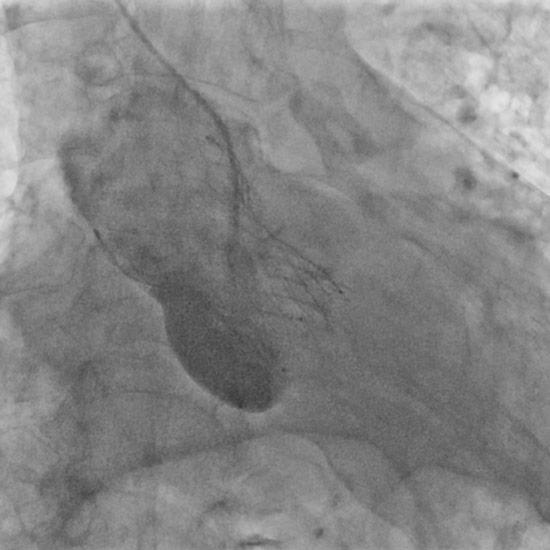

A 34-mm Evolut transcatheter aortic valve (TAV) (Medtronic) was deployed with a good result (Figure 1G). Closure of the femoral access site was uneventful (Figure 1H).

Figure 1G: Implantation of self-expanding transcatheter aortic valve.